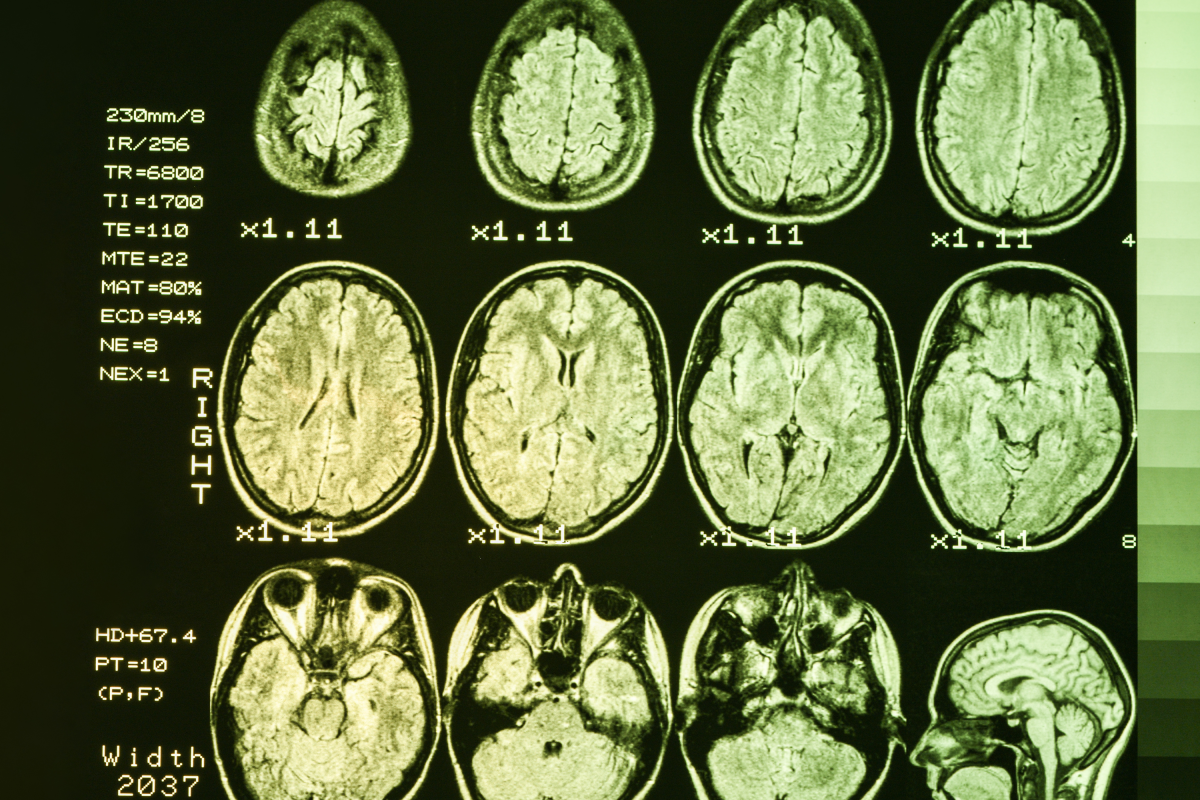

• The new treatment, AMT-130, is a form of gene therapy injected into the brain.